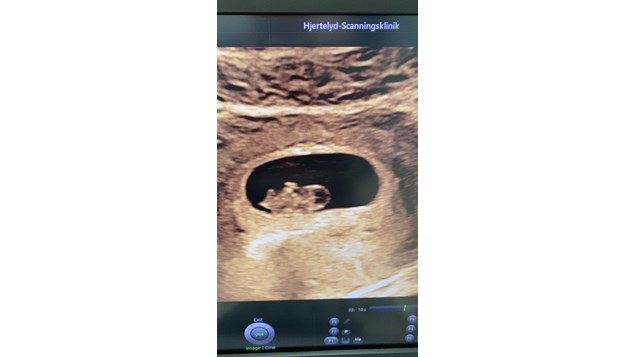

Se hele opslaget på Ensemble Midtvests FacebooksideDet lille spirende liv uge 8 💓 Det lille fine fosteranlæg her er bare 17,5 mm lang. Det svarer til graviditetens uge 8+1. Se de små lysende prikker i brystet - det er bittesmå hjerteklapper 🤩 Aller...

Se hele opslaget på Hjertelyd - scanningsklinik for gravides Facebookside🔥 Kom og få varmen til FAMILIEGUS 👨👩👧👦 ...måske her i weekenden 😉 - lørdag og søndag kl. 11.00 🔥 Hænger dine børn også med mulen, når saunadøren bliver lukket - og de ikke får lov til at k...